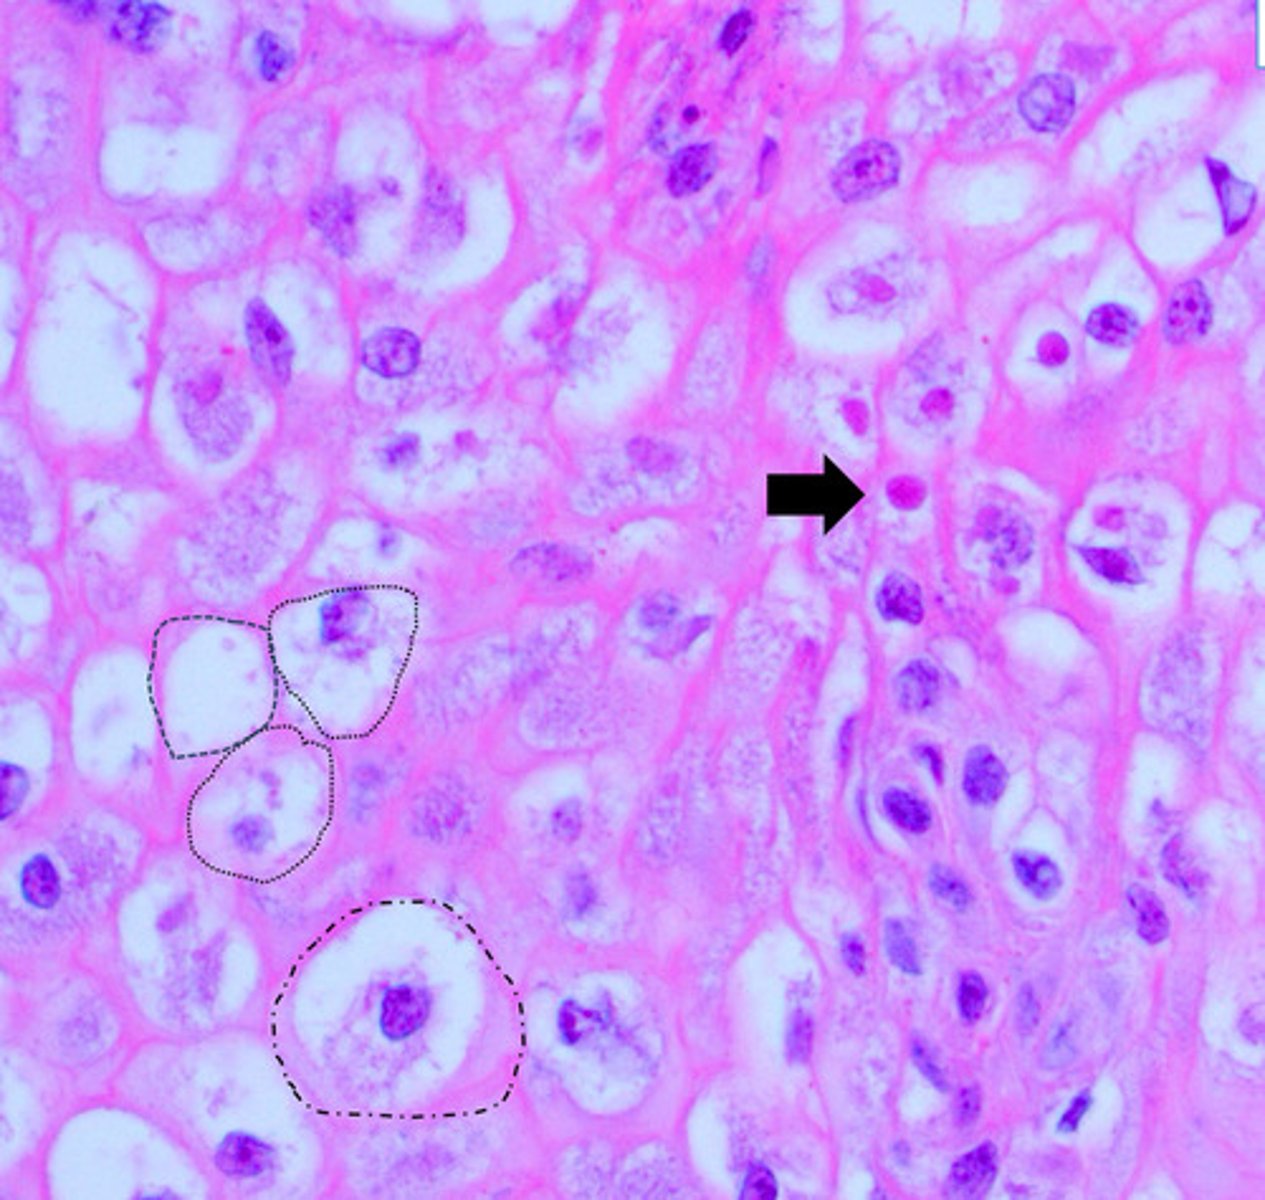

pyknosis

Identify the black circle?

Karyorrhectic cells

Identify the green circle?

karyolytic cells

Identify the Blue circle?